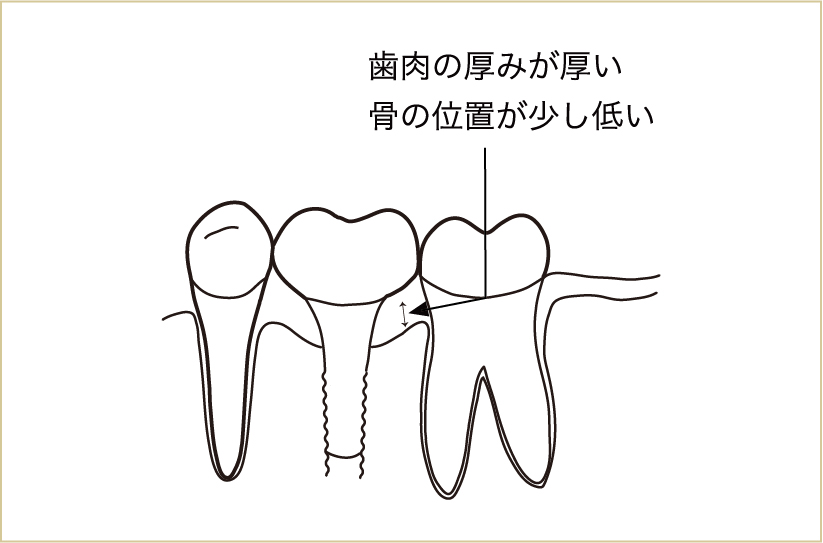

インプラントによる治療は、うまくいっている場合には自分の歯と見分けがつきづらいものですが、それでも実際には違いがあります。

外から見て周りの歯との違いが分かり難くても、実際には違いがある。それを理解することが長持ちさせるための第1歩となる。

隣同士の歯よりも骨の高さは少し低いことが多く、その分歯肉の厚みが厚いのです。

この歯肉とインプラントが接する部分は、通常の歯と同様に結合している部位もあります。しかしその結合も、全体的には歯と歯肉の付着に比べて弱いものであることがわかっています。